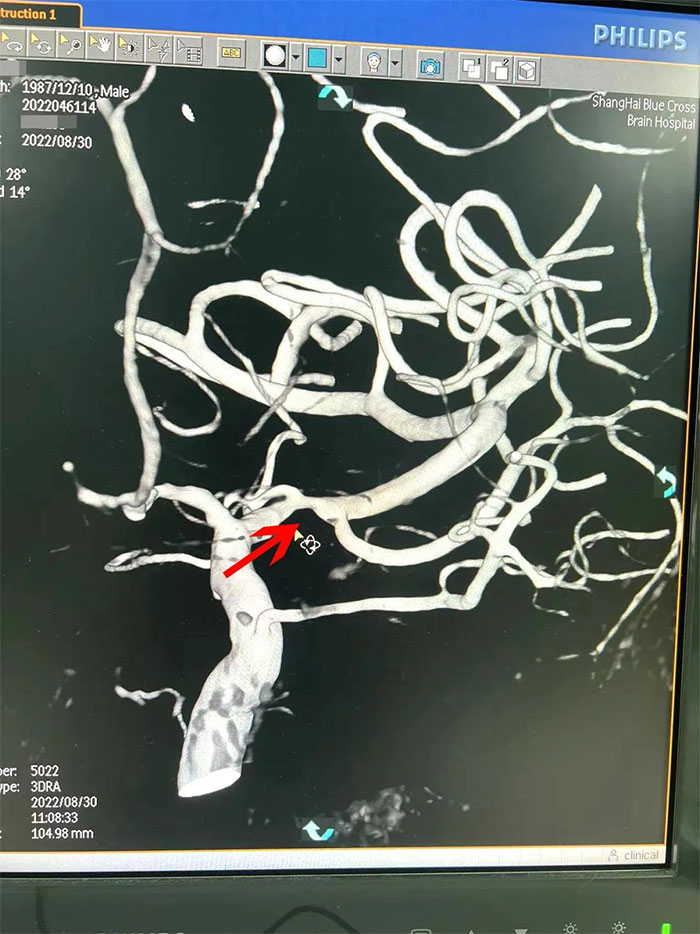

在检查中发现,周先生右侧大脑中动脉M1段闭塞,可见烟雾状异常血管网生成;左侧大脑中动脉M1段重度狭窄(约70%)。符合烟雾病的典型影像学特征。

▲ 检查发现烟雾状异常血管网

▲右侧大脑中动脉M1段闭塞,左侧重度狭窄